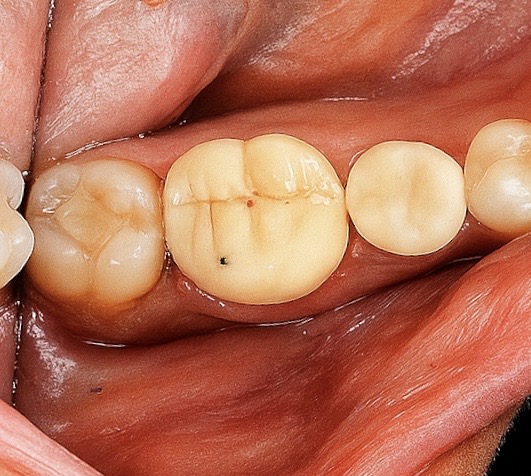

A full-coverage zirconia crown was fabricated to mimic occlusal morphology (Fig 4). Try-in confirmed marginal adaptation and occlusal contacts. Final bonding performed with Panavia V5 resin cement under isolation.

Radiograph confirmed ideal obturation, core adaptation, and marginal integrity (Fig 3). The final restoration blended esthetically and functionally with the dentition (Fig 5).

- Fig 4: Monolithic zirconia crowns ready for cementation.

- Fig 5: Final clinical result demonstrating functional and esthetic integration.